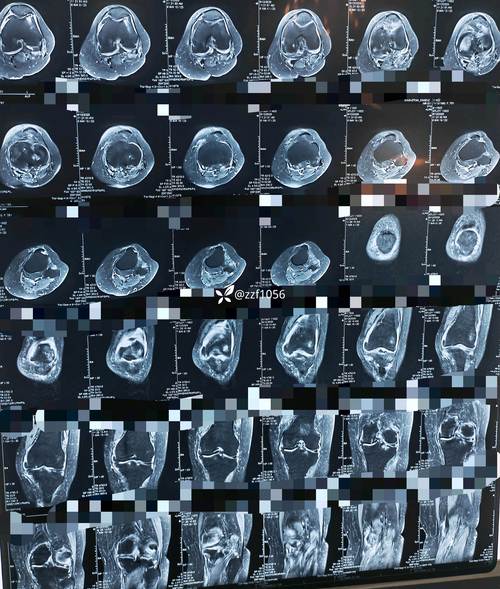

(图片来源网络,侵删)